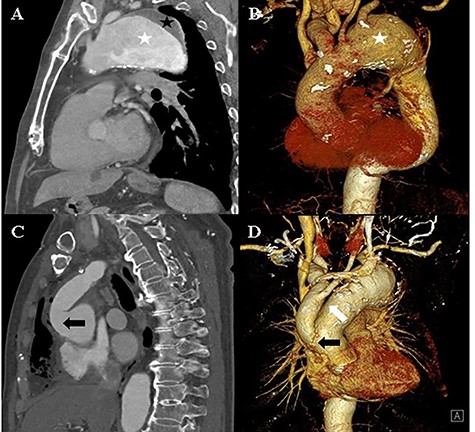

An 82-year-old man with a history of atypical chest pain was diagnosed with an aortic aneurysm with an eccentric mural thrombus at the distal arch. The thrombus had a maximum diameter of 70 mm starting directly below the ostia of the common carotid artery (Fig. 1). There were no abnormal findings, except for mild aortic regurgitation on preoperative echocardiography. We planned to perform a hybrid thoracic endovascular aortic repair and decided to carry out the debranching operation first. A type I hybrid arch debranching operation was performed; an 18-mm Gore-Tex graft was used from the ascending aorta to the innominate artery, and another 8-mm Gore-Tex graft was used from the innominate artery to the left common carotid artery in Spielvogel fashion (Fig. 1). There were no post-operative complications.

A and B: Computed tomography of the chest shows an aortic aneurysm (white asterisk) with a mural thrombus (black asterisk) at the distal arch. C and D: Post-debranching operative computed tomography of the chest shows the graft, which is directly sutured onto the ascending aorta (black arrow), and the graft used from the innominate artery to the left common carotid artery (white arrow).